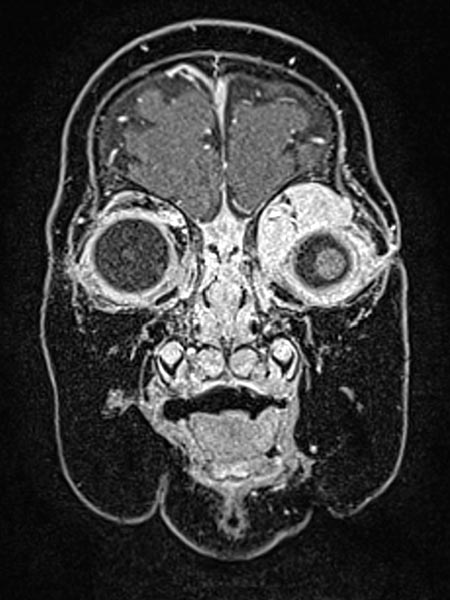

T1-weighted, coronal MRI after contrast depicts a homogeneous, strong enhancement in a solid, sharply demarcated tumor of the left eye. This is suggestive of an infantile hemangioma as part of the spectrum of vascular tumors.

T1-weighted coronal plane MRI after contrast administration in a slightly more dorsal plane shows extension of the contrast-enhancing solid mass well into the medial orbit of the left eye with displacement of the eyeball caudally and laterally.